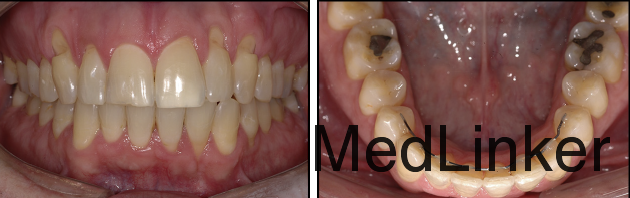

治疗计划:左下2行根管治疗,同时通过正畸重新定位。 治疗:32牙行根管治疗,下颌21*25不锈钢弓丝无力被动入槽稳定下牙弓(避开32牙,不结扎32牙),同时弯制带有根舌向转矩的19*25的TMA弓丝,前段只结扎到32牙,双侧后段插入第一恒磨牙颊管中,每个月加大转矩,持续5个月,在第五个月的时候,可见到32牙根尖已有软组织覆盖。此时上颌上矫治器,排齐整平。总疗程14个月。术后牙周探诊32牙唇侧牙周袋只有1mm。刺激痛症状消失。下颌4-4由16*22不锈钢弯制的舌侧丝保持。1年后复诊,效果仍然稳定。

1年后复诊,效果仍然稳定。 下前牙拥挤矫治后很容易复发,舌侧丝保持是比较推荐的方法,但也可能出现上述问题,非常值得引起我们的重视。有学者建议舌侧丝不要选择有弹性的弓丝,最好选用不锈钢弓丝,这样即使某些部位脱落,不会产生主动的力量致使牙齿移位。